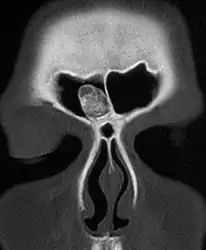

Medical imaging such as X-ray, CT scan and MRI show dense, clearly defined, round white tumors attached to bone.[1] They may be diagnosed when having medical imaging for another reason.[3] Osteomas of the paranasal sinuses and skull base can be diagnosed using CT-scan without intravenous contrast, allowing its size and relation to nearby important structures to be assessed.[3] A biopsy is not usually required.[3]

CT-scan skull: Osteoma of the frontal sinus